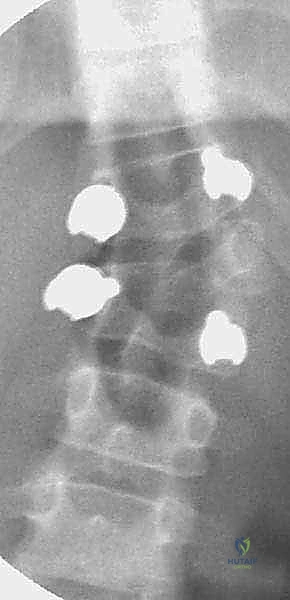

3. التصوير المقطعي المحوسب (CT Scan) ثلاثي الأبعاد

يوفر صوراً ثلاثية الأبعاد فائقة الدقة للتشريح العظمي المعقد. هذا الفحص يعتبر بمثابة "خريطة الطريق" للجراح، حيث يعتمد عليه الدكتور هطيف لتحديد حجم السويقات (Pedicles) بدقة بالغة، وتحديد مسار ومقاسات المسامير التي سيتم زرعها لتثبيت العمود الفقري.

الخطوة الثالثة: إدخال مسامير التثبيت (Pedicle Screws)

قبل استئصال الفقرة المشوهة، يقوم الدكتور هطيف بوضع مسامير التثبيت المصنوعة من التيتانيوم في الفقرة السليمة التي تعلو الفقرة النصفية، والفقرة السليمة التي تحتها. يتطلب إدخال هذه المسامير في عظام طفل صغير دقة هائلة، وهنا تتجلى خبرة الدكتور هطيف واستخدامه لأجهزة الأشعة التداخلية أثناء العملية (C-arm) لضمان المسار المثالي للمسمار دون المساس بالحبل الشوكي.